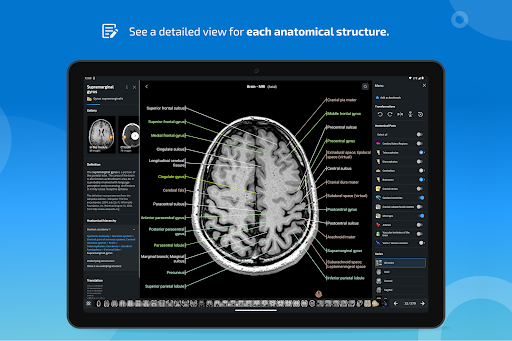

* تحسين عرض التفاصيل للأجزاء التشريحية لتسهيل التعرف عليها في صور الوحدات الحالية والوحدات الأخرى.

* تحسين رؤية تعريفات الأجزاء التشريحية

- يتم الآن عرض المصطلحات المتعلقة بالهيكل التشريحي في عرض التفاصيل - تمت إضافة